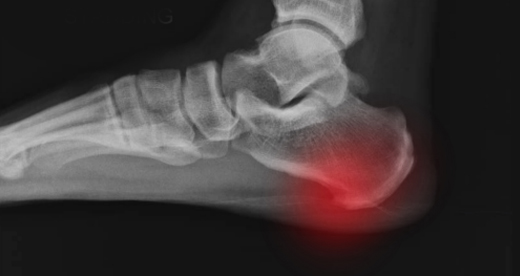

족저근막염

족저근막염이란 족저근막에 반복적인 미세 손상이 가해져 발생한 염증질환으로 발바닥에서

아치를 유지하며 발뒤꿈치에 띠 형태로 붙어 있는 근막에 발생하는 질환입니다.

반복적인 충격으로 인한 미세파열로 족저근막의 섬유화가 일어나고 염증이 발생하여 통증을 일으킵니다.